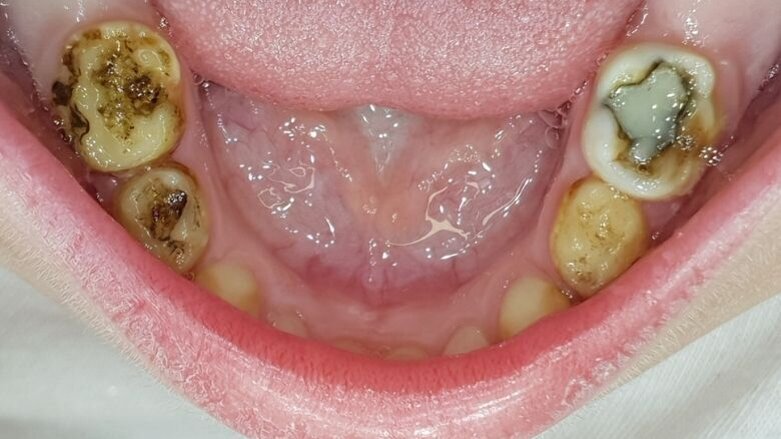

Een kind van vierenhalf jaar met multi-cariës werd verwezen voor behandeling onder narcose (afb. 6a-e). Klacht: lichte gevoeligheid .

Afbeelding 6a. Multi-cariës bij intake.

Afbeelding 6b. Multi-cariës bij intake.

Afbeelding 6c. Multi-cariës bij intake.

Afbeelding 6d. Cariëslaesies vrijgelegd en SDF aangebracht. Evaluaties van de zelfzorg bepalen de balans tussen causale therapie en symptoombestrijding.

Afbeelding 6e. Cariëslaesies vrijgelegd en SDF aangebracht. Evaluaties van de zelfzorg bepalen de balans tussen causale therapie en symptoombestrijding.